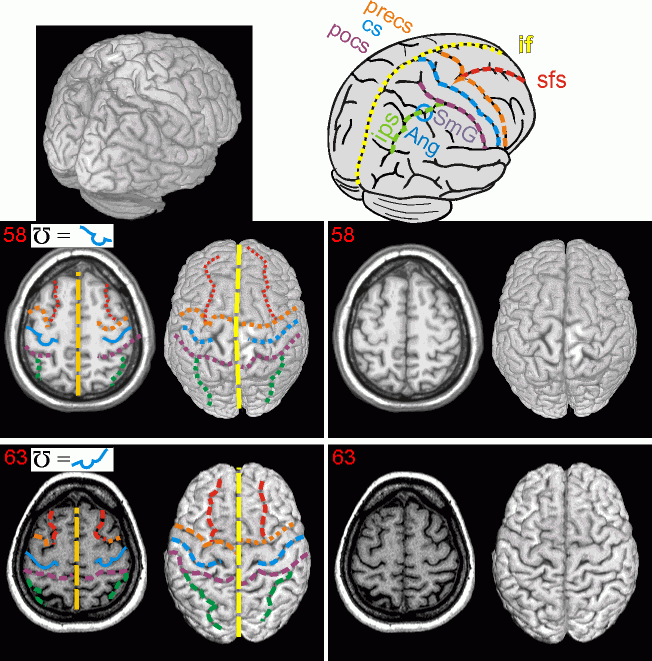

MR indication of central sulcus On 2월 1, 2013 By 수면제카테고리: 공부한 것 정리함 이 글 공유하기: X에 공유 (새 창에서 열림) X Facebook으로 공유하기 (새 창에서 열림) Facebook 좋아하기 가져오는 중... 관련